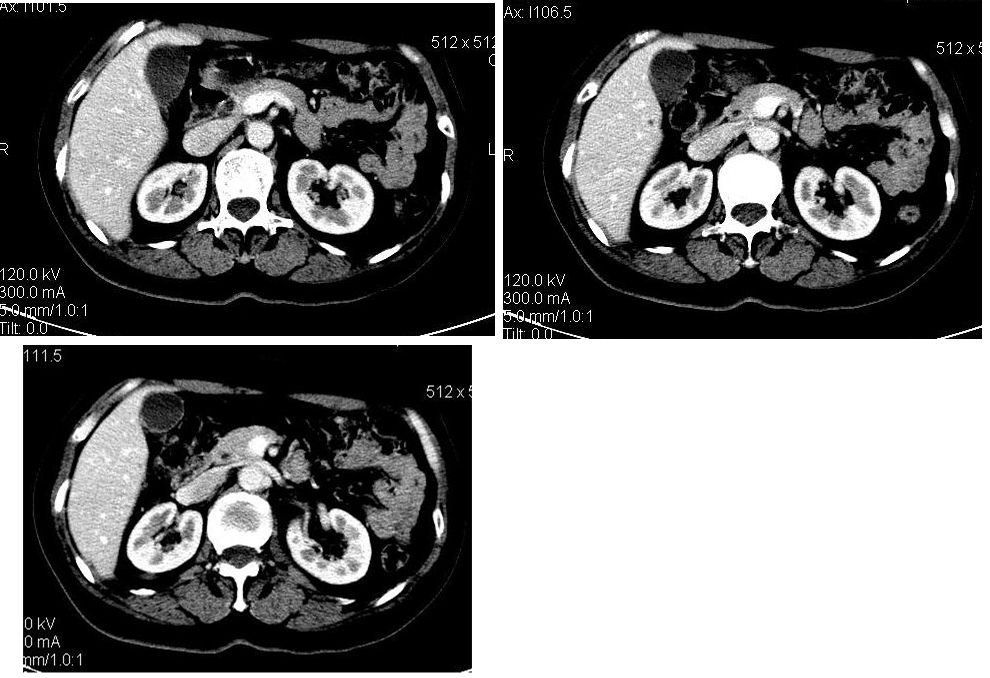

患者,女,65岁,住院准备甲状腺腺瘤用术,术前常规发现肝脏占位,ct增强扫描。

肝左叶内侧段肝癌,肝右叶可见小结节灶,并见强化,考虑转移.

肝脏ca伴肝脏多发转移

该患者去年9月份在我院ct检查,今年随访,患者家属介绍说上海中山医院做了一个什么检查考虑良性占位,后手术病理是血管平滑肌脂肪瘤。

学习了,这可能是脂肪含量少的血管平滑肌脂肪瘤,因血管丰富所以动脉期密度升高明显,但该患无肝硬化表现,所以,诊断肝癌,依据不足.谢谢上传.对今后工作是一个提醒.